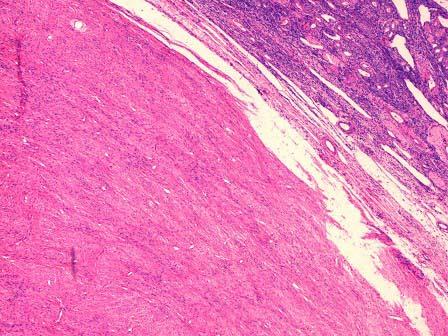

问题 女性,45岁,一年,腹水3月加重1月,妇检扪及左侧附件包块,质硬,行左卵巢切除送检。见卵巢一结节。直径3cm,切面灰白,略呈漩涡状。镜下见大量波浪状的胶原性结缔组织,小的梭形细胞排列成紧密的漩涡“席纹状”(如图),应诊断为 ( )

选项 A.卵巢纤维瘤 B.卵巢卵泡膜瘤 C.卵巢腺纤维瘤 D.卵巢粒细胞瘤 E.卵巢平滑肌瘤

答案 A